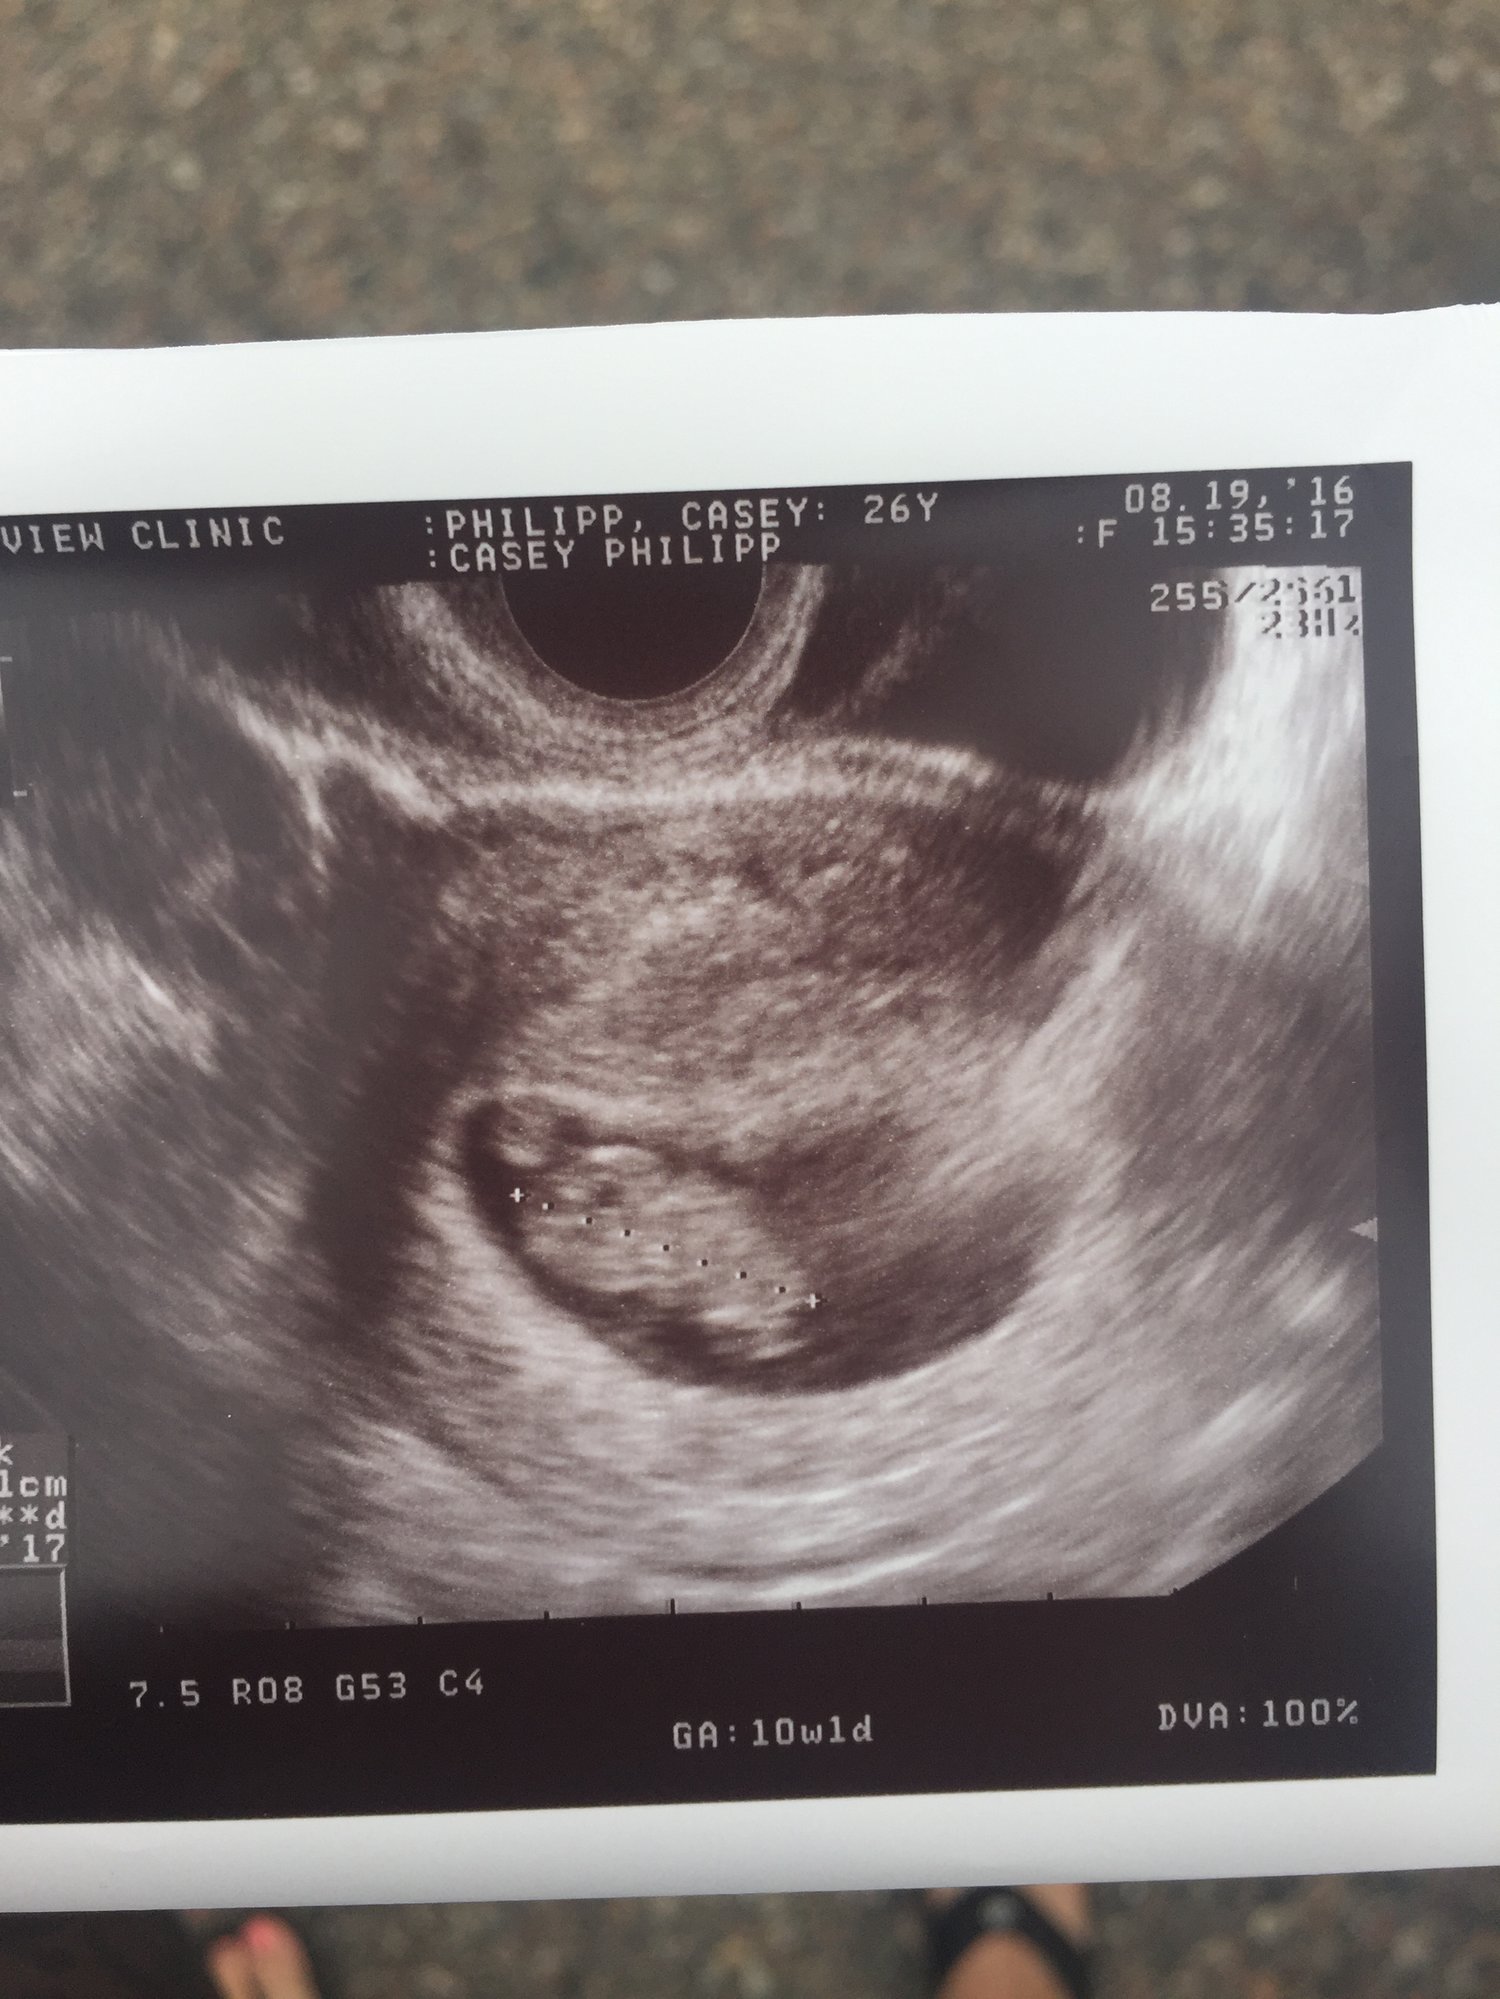

We got to see our little monkey last Friday!!! I know the US picture says 10 weeks, but that was based on my LMP. Baby P measured at 9 weeks 2 days!! The heart beat was incredible!!! Baby P is healthy and moving like crazy, so cool to see. September 8th is our first OB appointment!

Hey, girl. You might want to crop your photos so your name doesn't show.